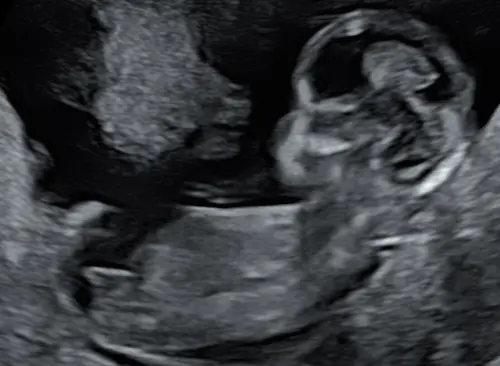

Weten jullie naar welke cirkel ik moet kijken? Dit is een 13,2 weken echo (tussen de beentjes) Bovenste lijken 2 streepjes van een meisje en daar onder lijkt een piemeltje.

Ik had bij mijn echo ook zo’n streep waardoor ik denk een jongen, maar als ik dan pottyshot foto’s zie van andere babies bij dezelfde termijn dan is het toch echt bij andere al beter te zien als het een jongen is.

Dus ik ben bang dat je nog een aantal weken moet wachten tot je zekerheid hebt 😅. Ga je een geslachtsbepalingsecho doen?